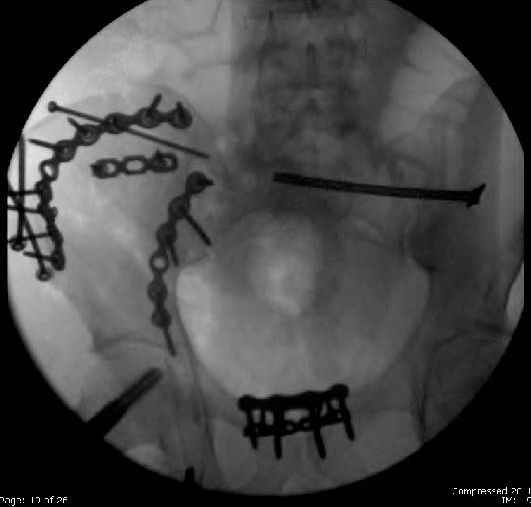

Here are the postop fluoros.

First exposed symphysis & clamped w/Faraboeuf as close to anatomic as possible.

Then extended to R ilioinguinal,really just the lateral window.

Reduced the triangular wedge piece of iliac wing to posterior intact ilium (crescent), held w/k-wire, then used 3-hole push plate to keep from moving, lagged from lat-med w 3.5 screw.

Then 6-hole plate along brim with 1 screw in R sacral ala. Then lagged 2 screws along crest A --> P. finally 10-hole plate along inner aspect of crest. R posterior ilium still a bit stepped off.

Symphysis then 'fine-tuned' & reduced as close as possible to anatomic (but, still with forward rotation of R hemipelvis - or, is it extension?) Accepted that amount of deformity and plated symph

with 4-hole symphyseal plate.

Fluoroed L SI joint and it seemed stable, but wide. So, applied c-clamp to try to squeeze down L SI joint (and note, on the last slide attached, that it's still wide), and got it closer. Single perc Iliosacral screw 40mm thread.

Applied second plate anteriorly on symphysis as I wasn't confident L SI was as stable as it could be and wanted to protect it better.

Thoughts? Thanks for the advice, it's appreciated.

Jeff